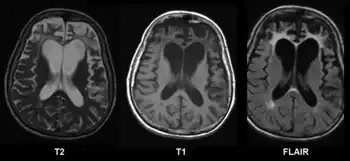

CT and MRI are most commonly used to observe the brain for cerebral atrophy. A CT scan takes cross sectional images of the brain using X-rays, while an MRI uses a magnetic field. With both measures, multiple images can be compared to see if there is a loss in brain volume over time.[20]

Cerebral atrophy can be hard to distinguish from hydrocephalus because both cerebral atrophy and hydrocephalus involve an increase in cerebrospinal fluid (CSF) volume. In cerebral atrophy, this increase in CSF volume comes as a result of the decrease in cortical volume. In hydrocephalus, the increase in volume happens due to the CSF itself.[20]